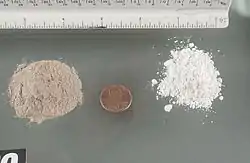

Administrada por vía intravenosa mediante inyección, la heroína puede ser entre dos y cuatro veces más potente que la morfina y es más rápida en comenzar sus efectos.[3] La heroína ilícita suele presentarse en un polvo blanco mate al que se añaden diversos adulterantes.[4] Una fracción importante de los consumidores de opioides, más de treinta millones de personas al año en todo el mundo según la ONU (2014),[5] consumen heroína, la cual está relacionada con un efecto narcótico pronunciado, se clasifica dentro de las drogas depresoras del sistema nervioso central y se caracteriza por producir una dependencia psicológica y física intensa a un ritmo muy acelerado, siendo considerada una de las drogas más adictivas y dañinas.[6]

- Sustancia pura - polvo blanco y cristalino.

- Producto bruto - amargo, de color gris- marrón de polvo en forma de pequeños cristales con un desagradable olor.[52]

Como resultado del procesamiento de estos materiales se forma un compuesto masa resinosa marrón o negra con un bajo contenido de diacetilmorfina y una gran cantidad de impurezas formadas durante la reacción, con efectos secundarios poco predecibles.